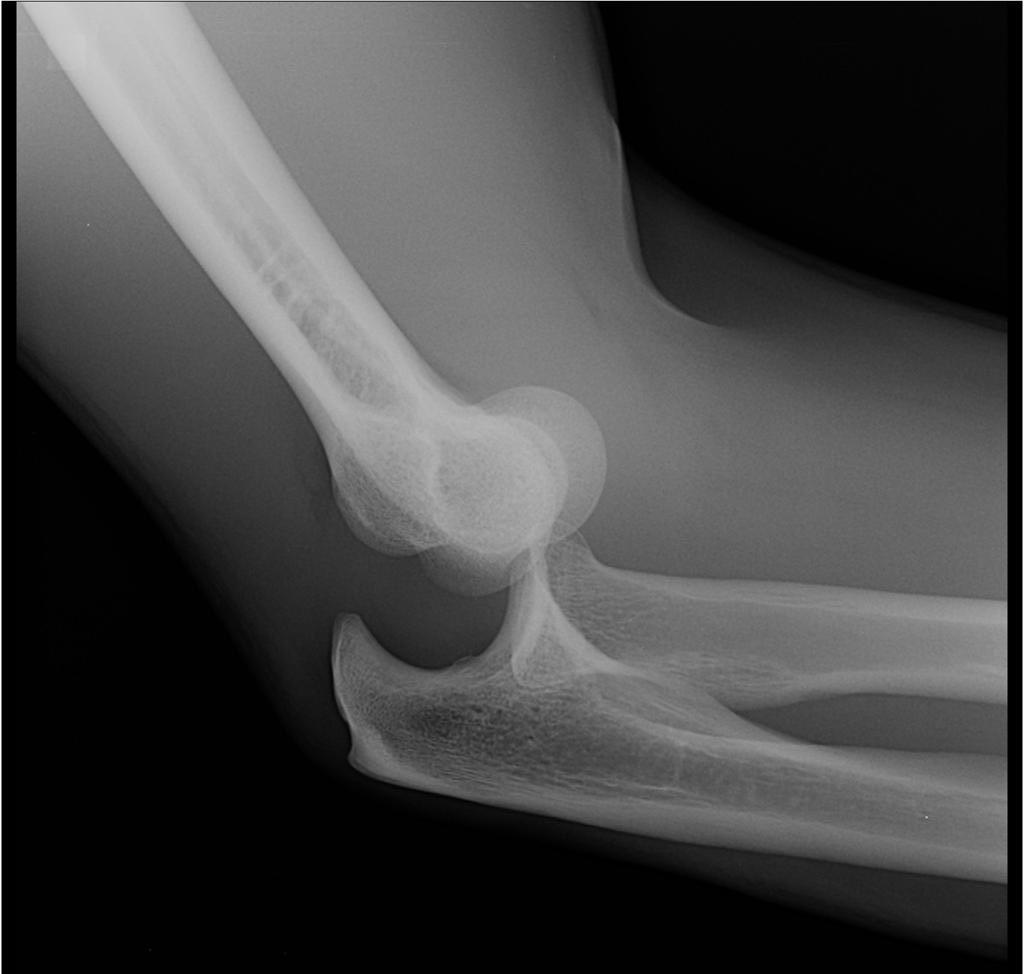

Артроскопія – це хірургічне втручання (операція), яка виконується для діагностики або лікування патології ліктьового суглоба. До речі, більше інформації про це можна дізнатися тут https://garvis.com.ua/ortopediya-i-travmatologiya/. Якщо рентген або магнітно-резонансна томографія не показують всієї “картини”, що відбувається, тоді артроскопію проводять в діагностичних цілях. В інших – тільки для лікувальних цілей.

Артроскопію при остеохондрозі проводять плечелоктьову артропластику, яка дозволяє пацієнтові швидше проходити реабілітацію. При переломах ліктьового суглоба також проводять артроскопію. При цьому м’які тканини практично “не страждають”, біль стає менш гострою і період реабілітації проходить швидше.